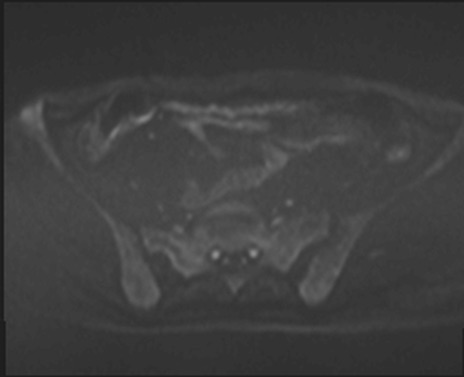

MRI(4日後)